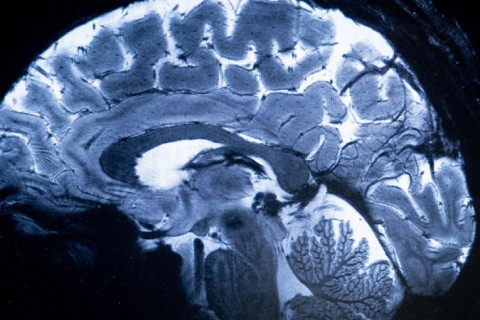

Psiquiatra chama atenção sobre os sinais que demostram que os jovens estão precisando de auxílio para lidar com a saúde mental